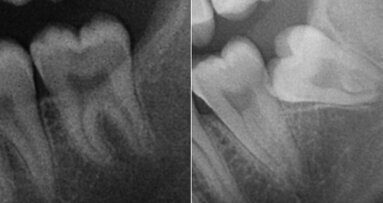

PHILADELPHIA, U.S.: Taste disorders and other neurosensory defects have been reported postoperatively in a number of patients who have undergone extraction of the mandibular third molars. Although taste deficits are generally expected to resolve within one year, the long-term effects of the surgical procedure remain unknown. A recent study conducted by researchers at the University of Pennsylvania in Philadelphia has challenged the notion that third molar extraction only has negative effects on taste, as it found that patients who underwent the dental procedure had improved taste abilities decades after the surgery.

The researchers compared data from 891 patients who had undergone third molar extractions (on average two decades earlier) with data from 364 individuals who had not undergone the surgical procedure.